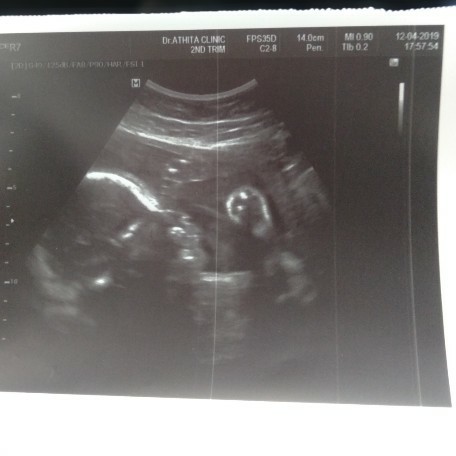

แม่ๆบ้านไหนกำหนดคลอด เดือน กรกฎาคม รู้จักเพศลูกกันยังเอ่ย แม่บ้านนี้ยังไม่รู้เลย?